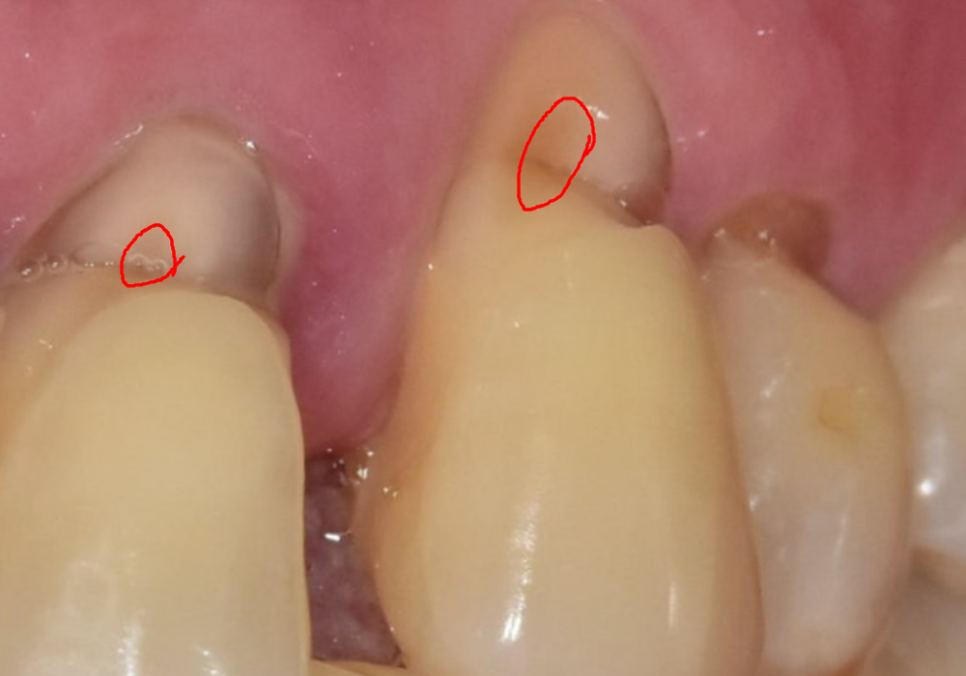

얼마 전 저희 치과를 찾으신

고령 환자분의 사례를 소개해 드릴게요.

이 환자분은 치아 뿌리 쪽이

아주 깊게 패어 있는 모습인데요.

오랜 세월 동안 마모가 서서히 진행되어,

육안으로 봐도 치아 안쪽의 신경이

드러날 정도로 심각한 상태였습니다.

보통 이 정도로 패여서 신경이 노출되면

물만 닿아도 자지러지게 아픈 게 정상이에요.